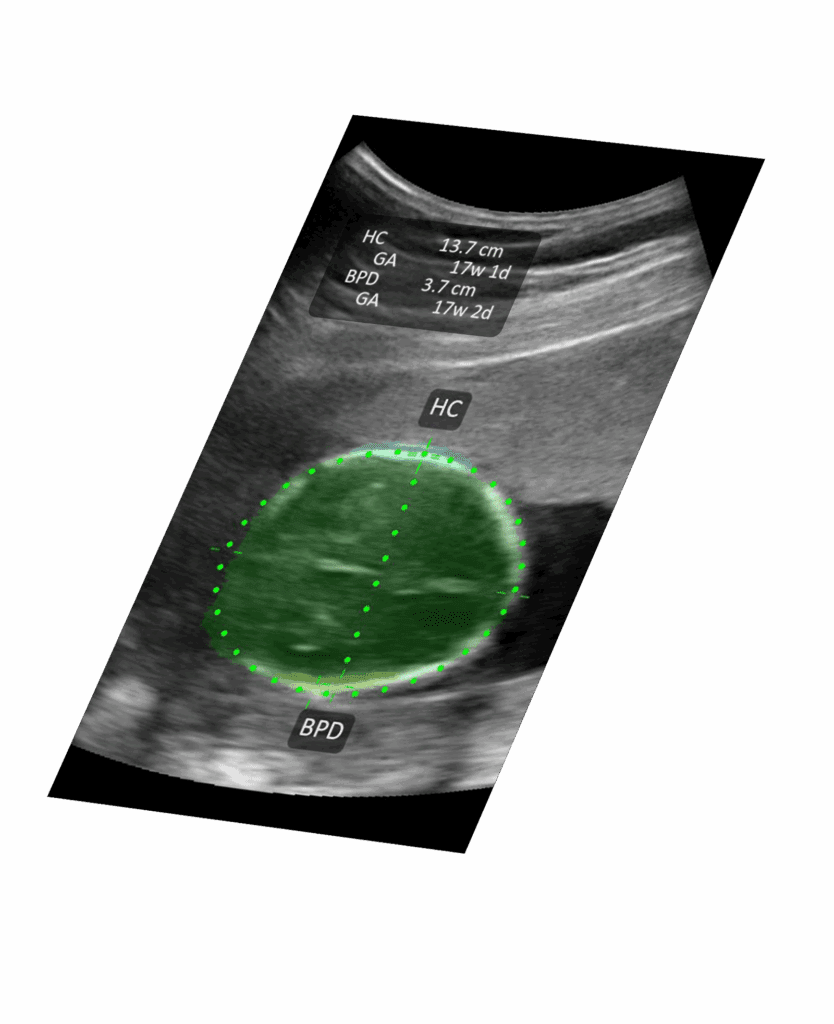

Mode-T™ enseigne pendant que vous scannez. Voyez instantanément l'anatomie étiquetée, pour que même les utilisateurs novices puissent interpréter les images et prendre des décisions en toute confiance.

Accélérez l'Apprentissage

Les structures anatomiques clés sont automatiquement mises en évidence et étiquetées pour réduire le temps d'interprétation.